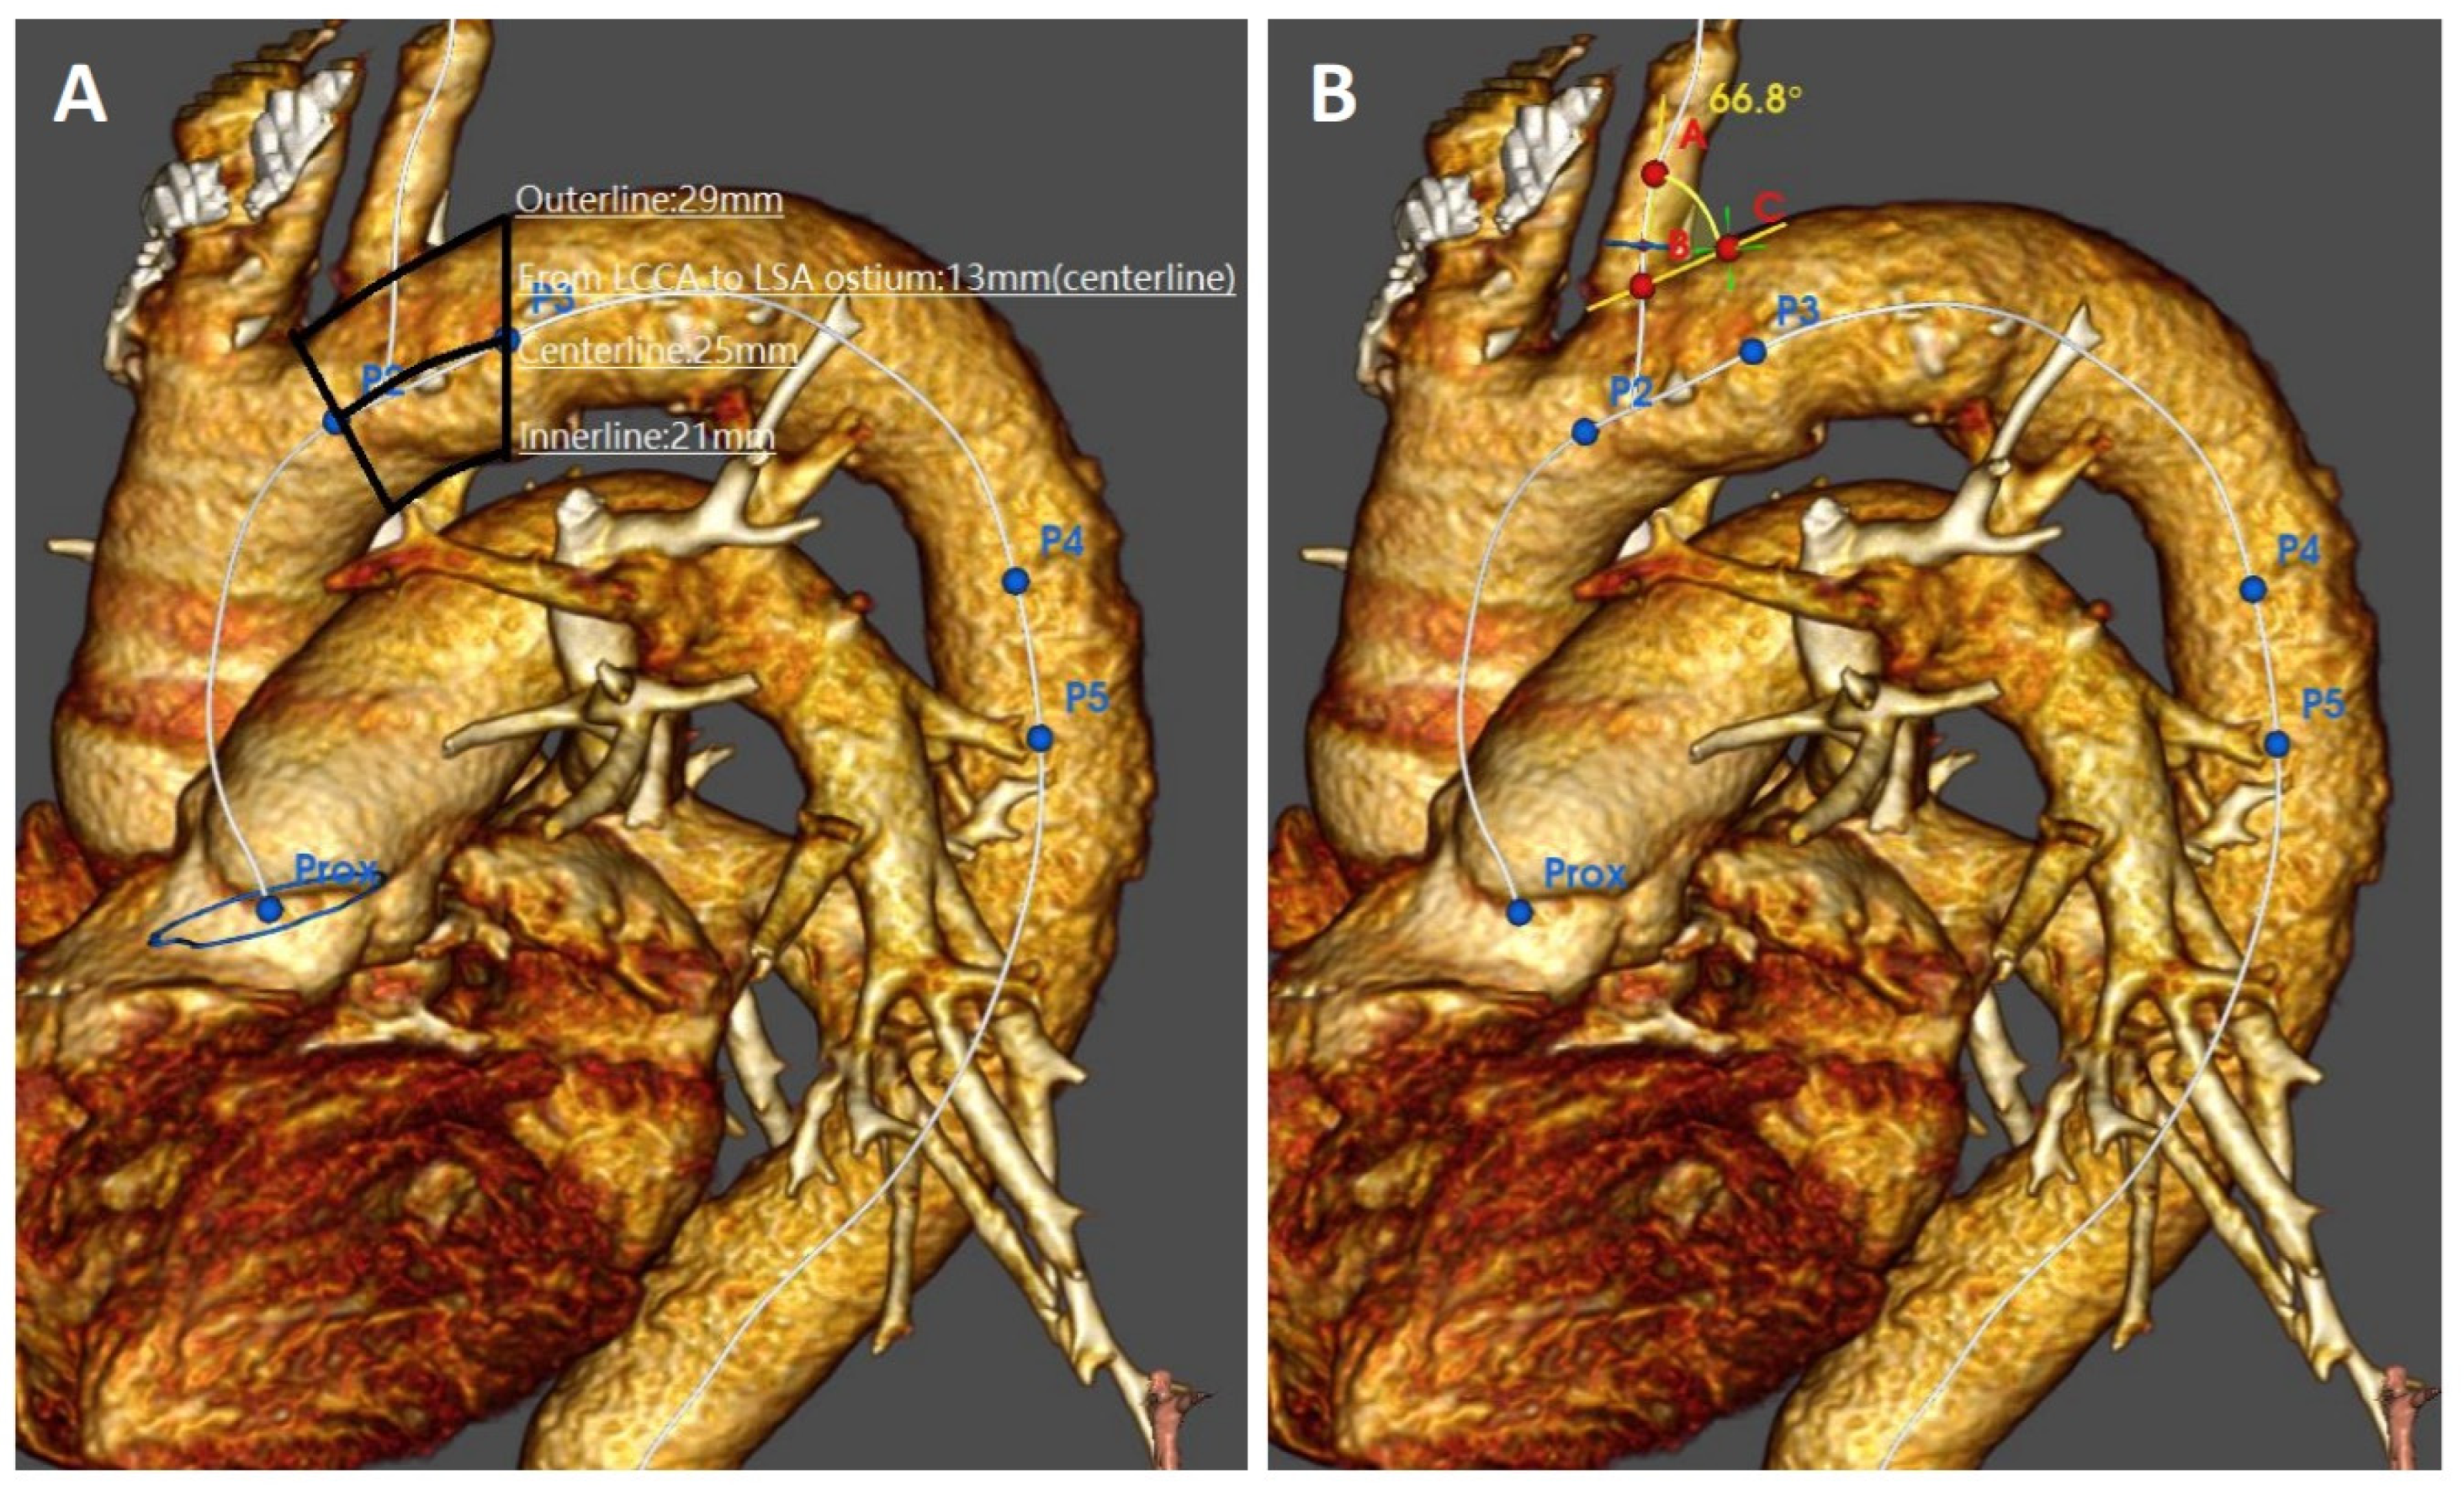

2.3. Imaging Analysis

| LSA angulation, mean ± SD (degrees) | 51 ± 15 (32–92) | 35 ± 17 (12–83) | 0.009 |

| PLZ outer curve, mean ± SD (mm) | 26 ± 10 (11–50) | 29 ± 14 (9–59) | 0.580 |

| PLZ centerline, mean ± SD (mm) | 23 ± 8 (10–42) | 23 ± 10 (8–43) | 0.902 |

| PLZ inner curve, mean ± SD (mm) | 20 ± 7 (7–39) | 19 ± 7 (5–33) | 0.499 |